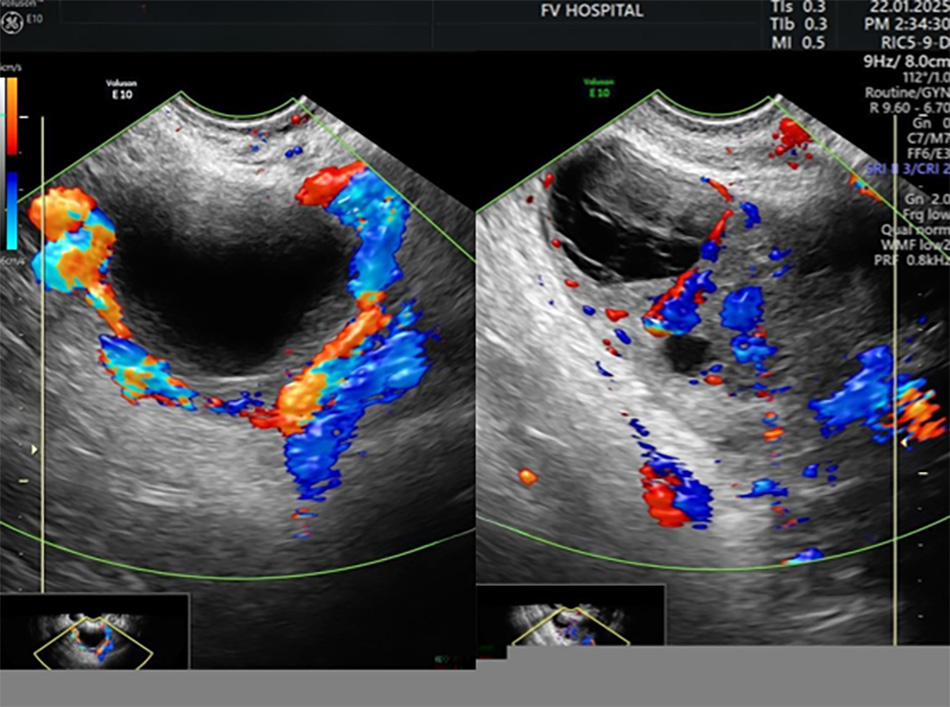

The ultrasound image of the ovary shows normal blood flow after one week of follow-up (the left side is normal, while the right side had previously been twisted).

The untwisting procedure lasted approximately 30 minutes, with the actual intervention taking less than 10 minutes. Two days after surgery, an ultrasound confirmed that blood flow had returned to the ovary. The patient was discharged two days later.

A follow-up one week later confirmed that the blood vessels were recovering well, the ovary had nearly returned to normal, and the foetus was developing healthily. The patient’s family was overjoyed and deeply grateful for the decisive decision made by the doctor.